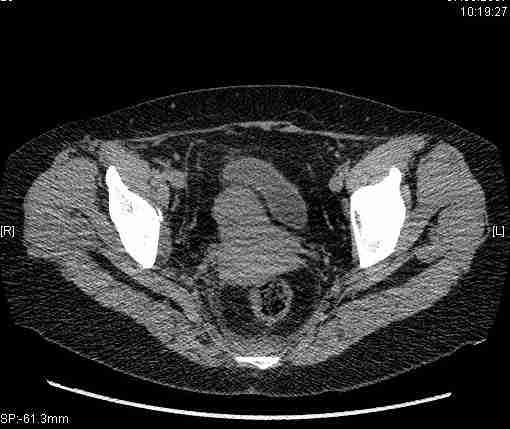

Удалось сегодня вывести пациентку в соседнюю больницу, где есть кт. Срезы сделаны только горизонтальные.

|